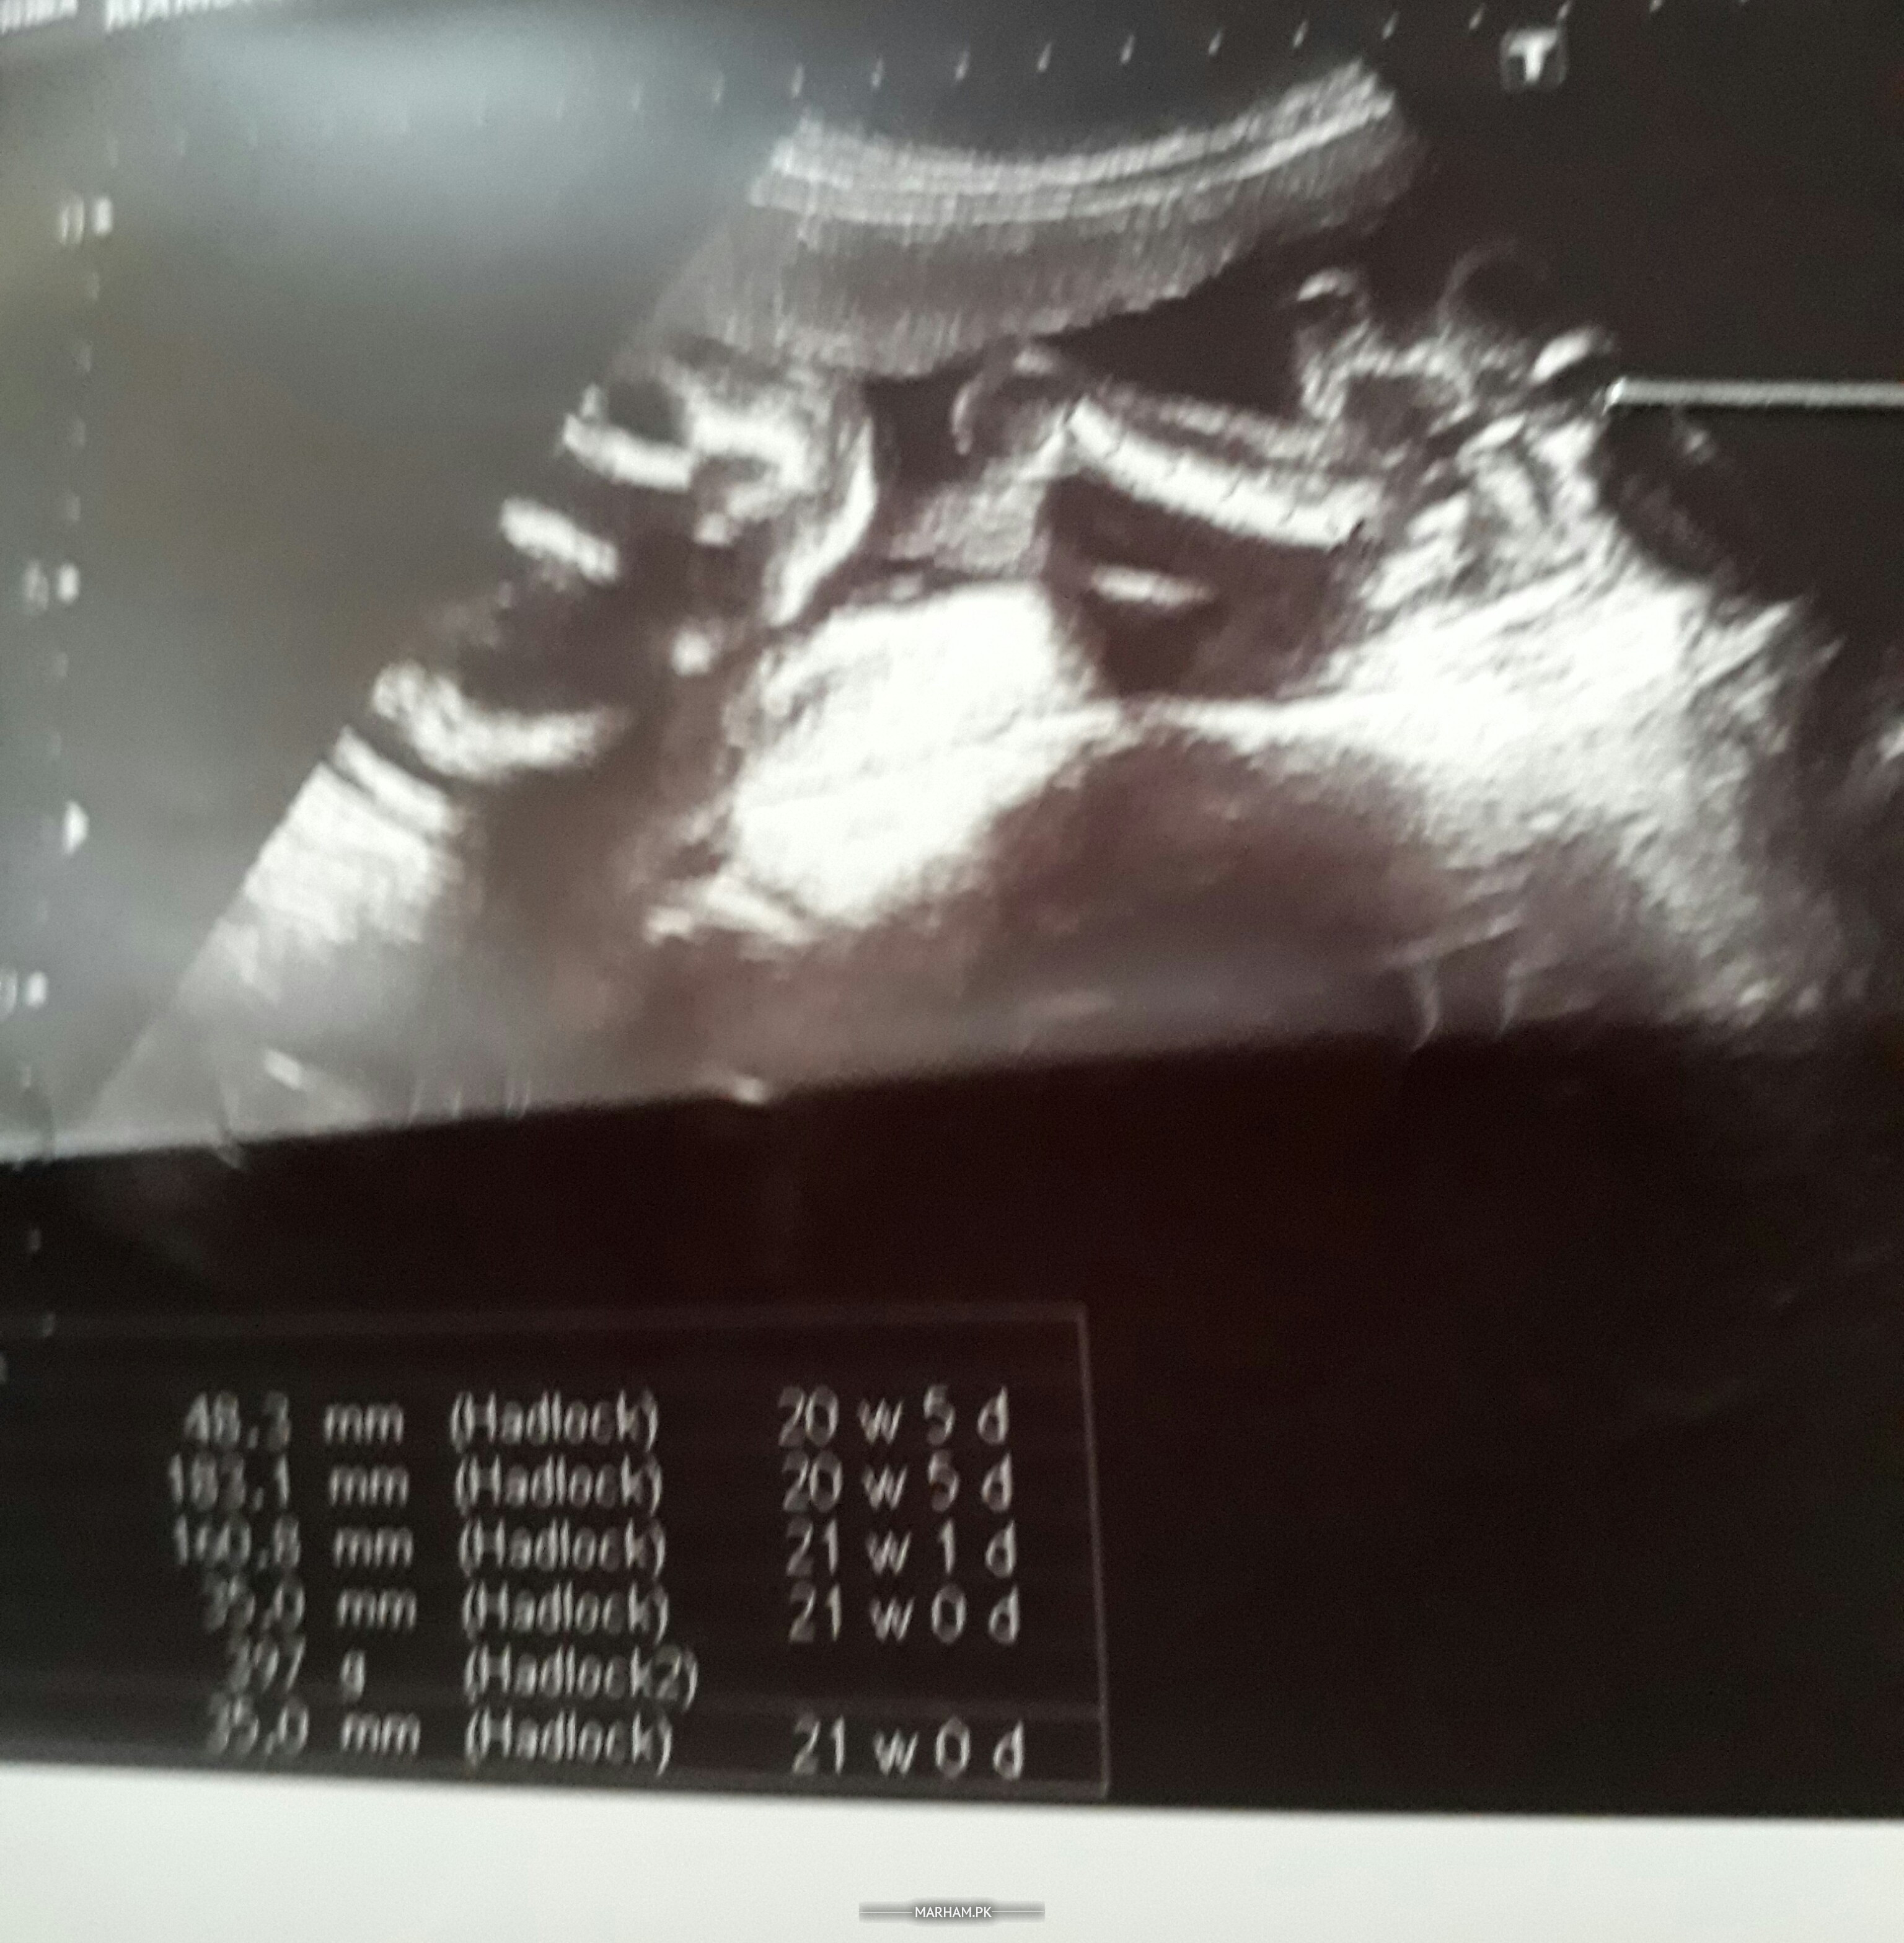

I am 23 weeks and 6 days pregnant but still not feeling movement I did my anomoly scan at 21st week which shows i have anterior upper segment should I do ? I am really worried about baby's he ok

Is every thing ok in my ultrasound report

Anterior uppr segment placenta means placenta is covering your uterine os.